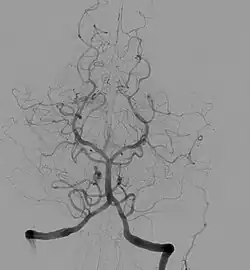

Diagram of the arterial circulation at the base of the brain (inferior view), the circle of Willis is drawn in the upper half. Blood flows up to the brain through the vertebral arteries and through the internal carotid arteries.

The arteries of the base of the brain. Basilar artery labeled below center. The temporal pole of the cerebrum and the cerebellar hemisphere have been removed on the right side. Inferior aspect (viewed from below).